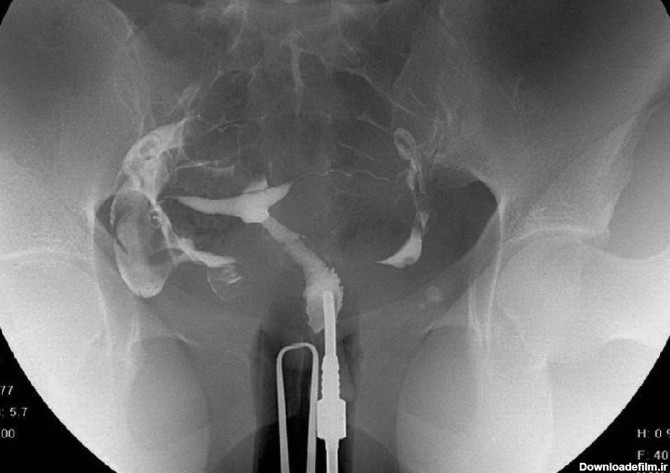

برای بررسی علت تأخیر باروری، باید سلامت اندامهای تولید مثل مورد ارزیابی قرار گیرند؛ یکی از روشهای تشخیصی که برای بررسی رحم و لولههای رحمی درخواست می شود، هیستروگرافی است. با این تست، پزشک از وضعیت داخلی رحم و لوله های رحمی مطلع میگردد و با توجه به نتایج حاصل از تست، در مورد نحوه درمان تصمیم خواهد گرفت. انجام این تست در ارزیابی ناباروری بسیار مهم است.